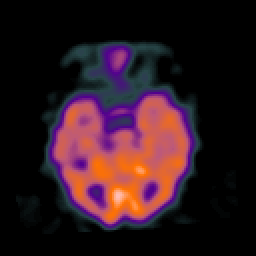

Normal aging, overlay -- Slice #20

[Home][Help][Clinical] Slice 20